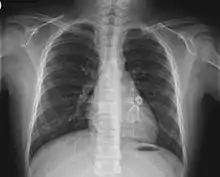

| RS | Shortness of breath,[31] influenza-like illness, pleural effusion, atelectasis |

- Electrocardiogram may show evidence of ventricular dysfunction or, occasionally, arrhythmia due to myocarditis.

- Echocardiogram may show subtle coronary artery changes or, later, true aneurysms.